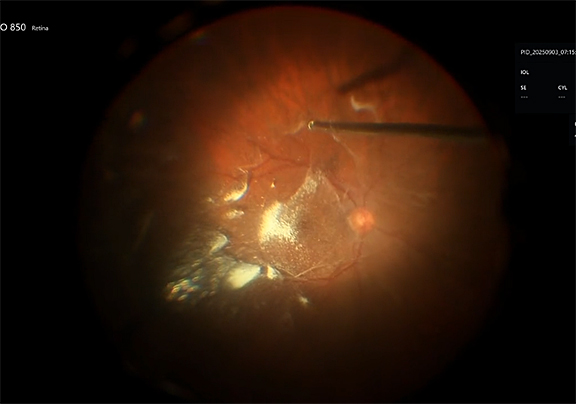

Dilute ICG dye is introduced into the posterior pole. A drop-on contact lens viewing system is placed and the 25-gauge ILM forceps are used to peel the small areas of overlying epiretinal membrane as well as the underlying internal limiting membrane in a circumferential fashion to the hole. Here we are using a pinch and peel technique.

Now we switch to use the cutter on aspiration mode. Using the vitrectomy probe on aspiration only, the ILM flap is then peeled further. The amputated pieces are aspirated.

We switch back to the 25-gauge ILM forceps to complete peeling the ILM to release all of the traction on the fovea.